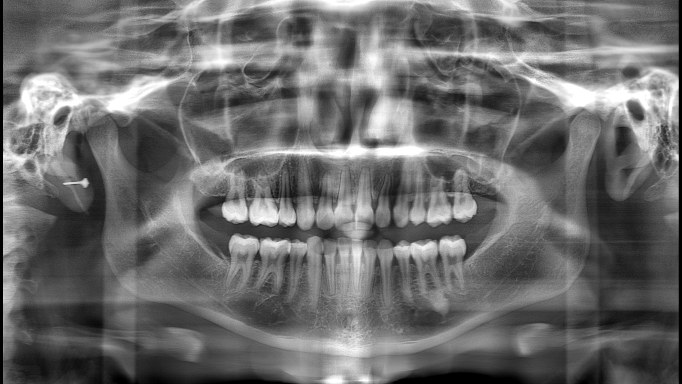

▲“ "The Effect of 'PD' Technology in Panoramic Images"